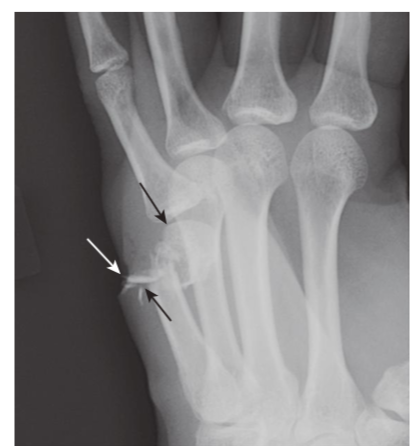

Jones fracture, base of 5th metatarsal.

A Jones fracture is a transverse fracture of the base 5thmetatarsal (white arrow). It occurs about 1 to 2 cm from the tuberosity of the 5thmetatarsal (black arrow)and frequently takes longer to heal than an avulsion fracture of the tuberos- ity. It is caused by plantar flexion of the foot and inversion of the ankle.